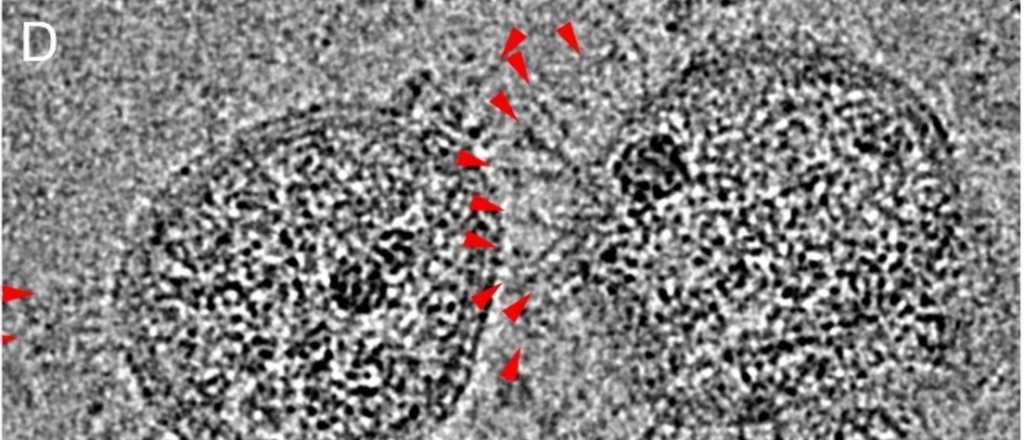

Científicos chinos han captado las primeras imágenes que muestran la apariencia real del nuevo coronavirus mediante un microscopio electrónico que analiza muestras a temperaturas criogénicas para inactivar la cepa de ese microorganismo.

Esos especialistas observaron a través del dispositivo Cryo-EM que las partículas de su virión (la unidad estructural del virus), son "casi esféricas o moderadamente pleomórficas", así que este coronavirus tiene la capacidad de alterar su forma en función de las condiciones ambientales.

Además, estos expertos revelaron que sus picos, la parte de los virus que les permite adherirse a las células, tienen forma de uña hacia el exterior con un cuerpo largo incrustado en la cubierta.